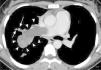

La tomografía axial computarizada (TAC) y la resonancia magnética (RM) se consideran las pruebas complementarias más útiles para diferenciar una tumoración de un trombo2,3. En ambas enfermedades, la TAC con contraste muestra defectos de llenado intraluminal poco atenuados, y la diferenciación radiológica entre un tumor de AP y un tromboembolismo puede ser difícil4. Los hallazgos indicativos de tumor de AP en la TAC (fig. 1) son los defectos de llenado hipodensos con atenuación no homogénea que ocupan la totalidad de la luz de la arteria acompañados de un incremento del diámetro del vaso; presencia de tejido blando circundante que ocupa toda la luz de la AP; distensión vascular debida al crecimiento del tumor; AP periféricas de aspecto arrosariado; extensión extravascular del trombo; y captación variable y retardada del contraste en la angiografía por TAC2,4.

Tomografía axial computarizada con contraste de una mujer de 35 años de edad que presentaba disnea, dolor torácico y hemoptisis de varios meses de evolución. Un defecto de llenado extenso, irregular y con atenuación no homogénea ocupa la arteria pulmonar principal derecha y se extiende hacia sus ramas, que muestran aumento de sus diámetros (puntas de las flechas). Obsérvese también el aspecto arrosariado de una arteria periférica (flechas).